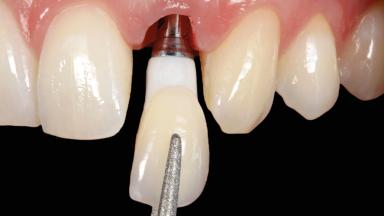

In this case, Arndt Happe describes how he achieved a stable outcome at 5 years by giving careful attention to the coronal aspect of the transmucosal area of the provisional, creating a slim emergence profile.

A healthy 31-year-old female patient presented with a failing maxillary left lateral incisor crown. The crown regularly loosened, and the remaining tooth was neither restorable nor rational to treat. The patient had a high smile line, a medium soft tissue biotype with a compromised mesial papilla (shorter than the contralateral one), and a horizontal scar in the buccal soft tissue as a result of past periapical surgery.

| Implant-supported provisional restoration | Required, elevated esthetic and/or functional demands |